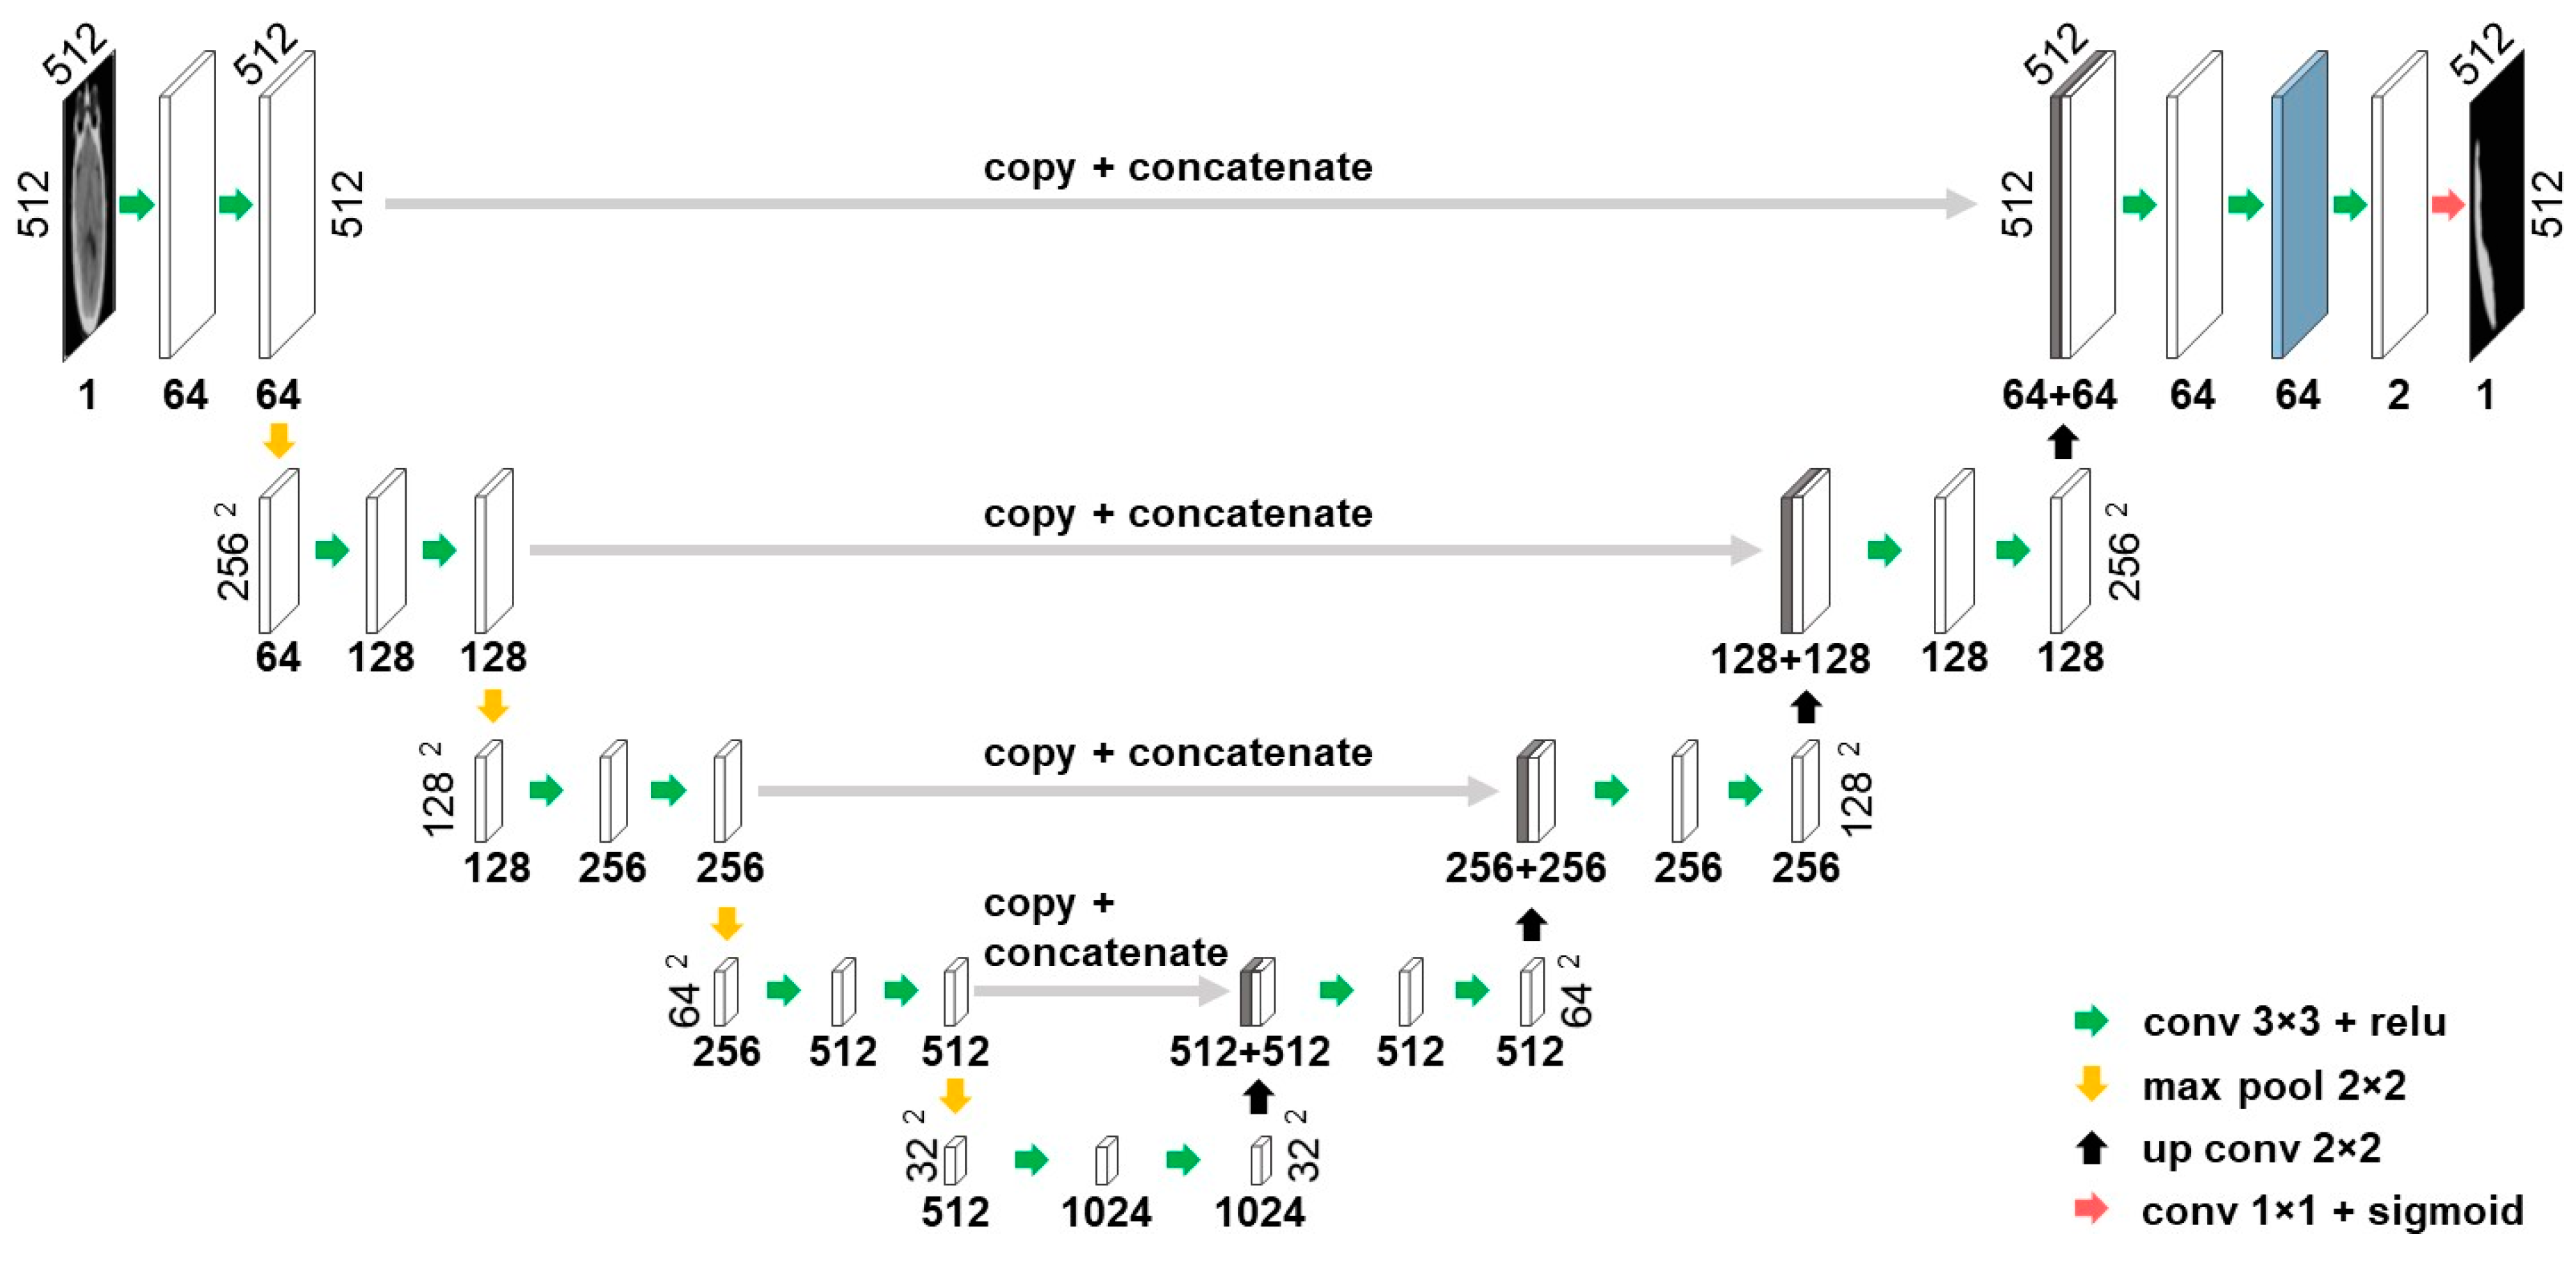

Deep Features

In this work, the U-net architecture was employed to extract data-driven deep features. The U-net architecture was proposed by Ronneberger et al. [

23] in 2015 and has subsequently become one of the most widely used convolutional neural network architectures for biomedical applications, specifically those with limited access to annotated data. First, a baseline U-net model shown in

Figure 5 was trained for SDH segmentation and then activations of the second layer before the output layer were employed as deep features. The layer used for deep feature extraction is marked by blue in

Figure 5 and yields 64 features for each superpixel. To ensure that deep features were not influenced by the test set,

n-fold cross-validation was performed, in which

n different models generated

n sets deep features. Later, the same cross-validation folds were used to train the random forest model.